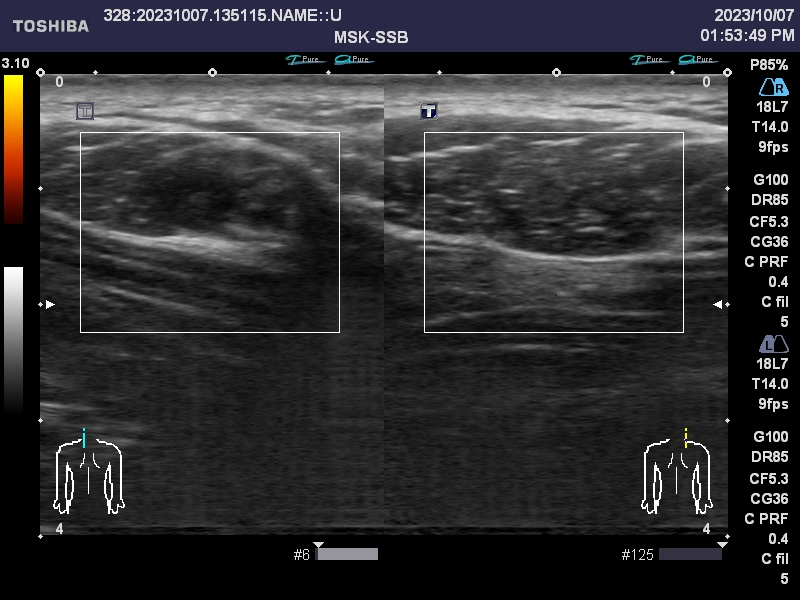

肩こりのエコー画像

当院ではエコーも活用しながら、筋肉や運動器の状態を確認し、状態の把握に努めています。